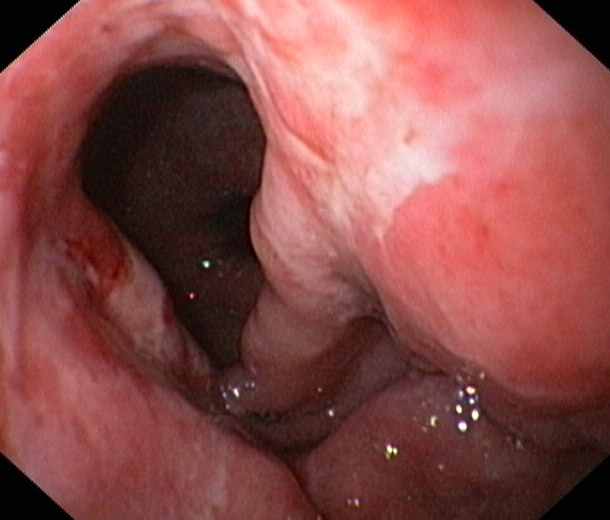

Oesophagus:

Oesophagus:A typical oesophageal cancer